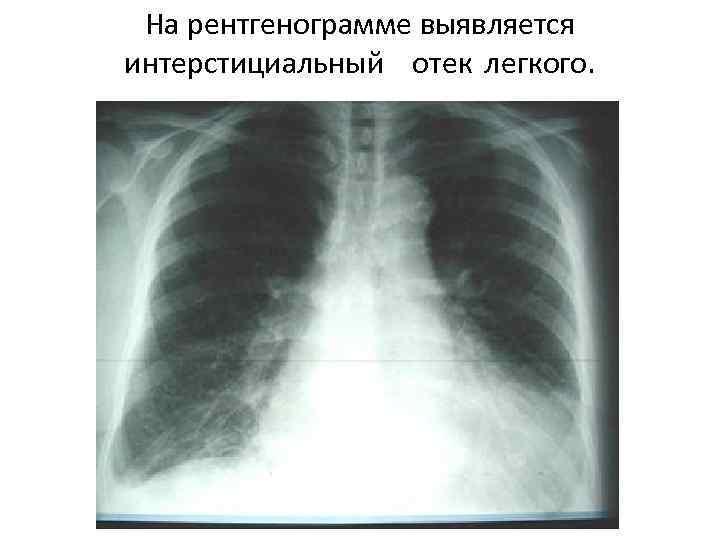

Изменения в легких Гиповолемия при шоке ведет к снижению легочного кровотока. Легкое при шоке характеризуется нарушением поглощения кислорода. Больные жалуются на удушье, у них учащено дыхание, снижается парциальное давление кислорода в артериальной крови, уменьшается эластичность легкого, оно становится неподатливым.

На рентгенограмме выявляется интерстициальный отек легкого.